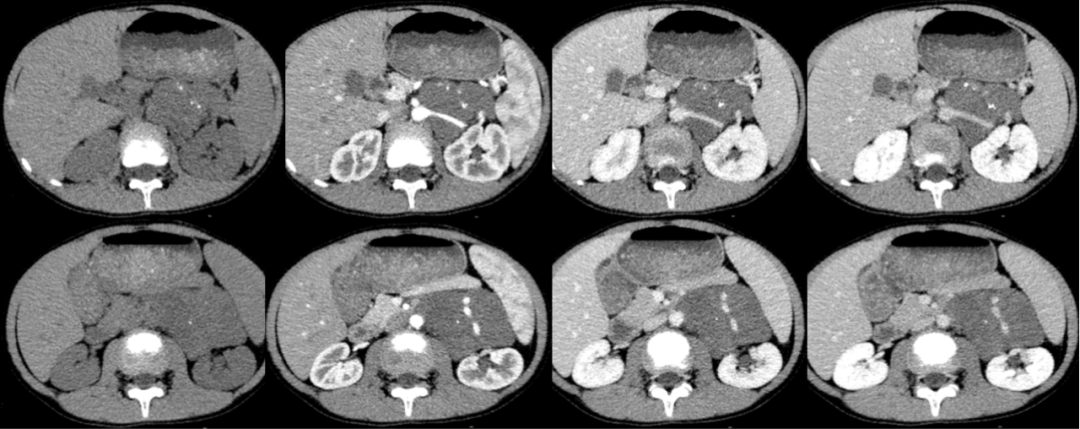

男,7 岁,因「发现左腹部包块 1 个月入院」。

影像描述:胰体尾部后方左肾前内方见团块样软组织密度影,大小约 7.6 cm×5.8 cm,CT 值约 36 HU,略呈轻度强化,其内见多发结节样钙化影,病变与左侧肾上腺分界不清,包绕左肾动静脉,未见变窄,其内另见左肾静脉分支迂曲走行。